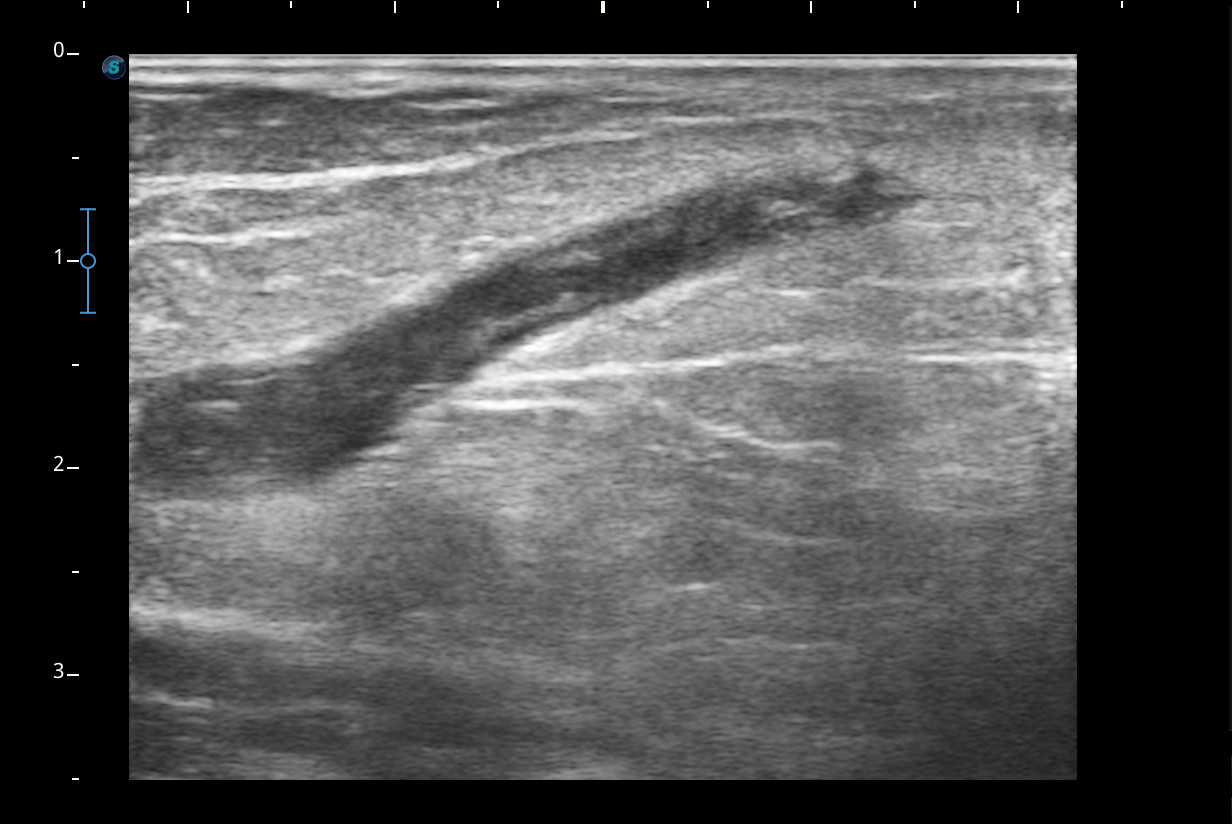

Hallazgos ecográficos

Se visualiza congestión del tejido subcutáneo del brazo y ocupación de la luz de la vena basílica del brazo por un trombo.

Diagnóstico: trombosis venosa de la vena basílica del brazo derecho. Concordancia con el hospital en el segundo tiempo que acude la paciente.